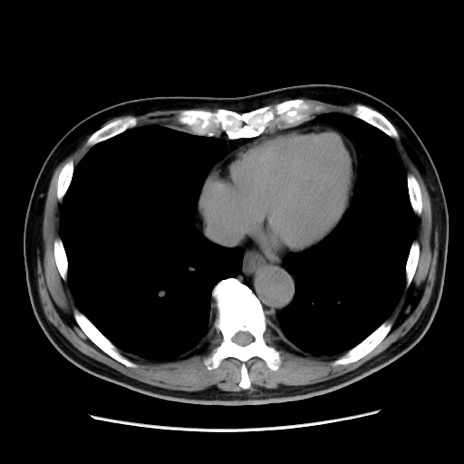

冠状断像

【症例】 70歳代男性

【主訴】 腹痛、嘔吐

【現病歴】 約1ヶ月前より間欠的に腹痛と嘔吐あり、当院消化器内科を受診したところCTで多発する肝臓のLDAを指摘され、精査中であった。以降は消化器症状は安定していたが、2日前より嘔気と腹痛があり、同日より排便・排ガスが消失した。改善認めず、 本日、救急外来を受診した。

【既往歴】 大腸ポリープ切除後。

【身体所見】意識清明・会話良好、BT 36.3℃、BP 127/80mmHg、 P 80bpm、腹部:膨満あり、平坦・軟、上腹部正中および下腹部正中に圧痛あり、反跳痛なし、筋性防御なし。

【データ】WBC 7200、CRP 0.77